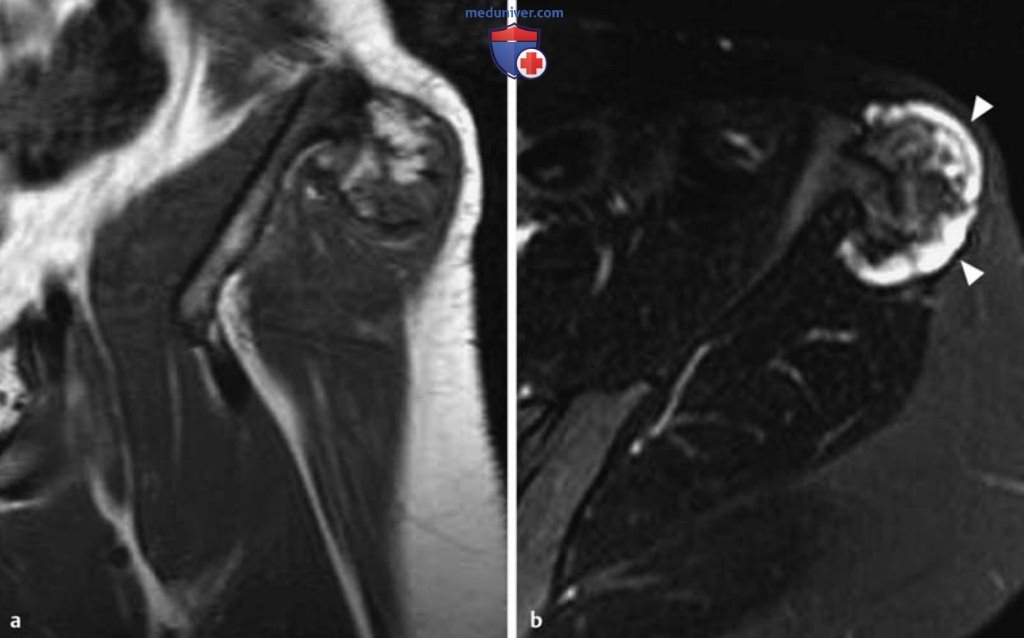

Рисунок 4. а, b Остеохондрома подвздошной кости, расположенная на ножке.

а Т1в-SE-изображение во фронтальной плоскости.

b Т2в-БЕ-изображение в аксиальной плоскости.

Отмечается непрерывный переход костномозговых пространств и кортикального слоя подвздошной кости на ножку патологического образования. Хрящевая шапочка имеет максимальную толщину примерно 1 см. Она изоинтенсивна мышцам на Т1 в-изображениях и сильно гиперинтенсивна на Т2в-изображениях. На Т2в-изображениях гиалиновый хрящ отделен от окружающих мягких тканей слабо гипоинтенсивным окаймлением (головки стрелок, b).